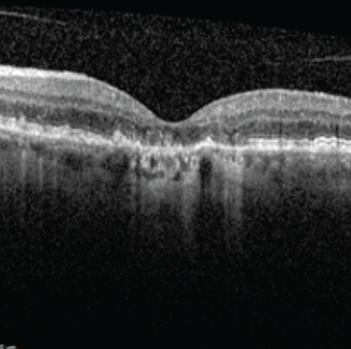

Le fait que vous ayez été dirigé vers un ophtalmologiste vous permettra d’obtenir un diagnostic formel de DMLA (ou d’éliminer d’autres affections pouvant affecter votre rétine). Les évaluations habituelles pour détecter la DMLA incluent un test de vision et un examen de la vue complet, y compris un examen de la rétine. De plus, vous devrez probablement passer un examen d’imagerie appelé tomographie par cohérence optique (TCO). Il s’agit d’un balayage laser non invasif du fond de l’œil. Il permet à votre ophtalmologiste de voir des zones de la rétine pouvant être endommagées ou en train de mourir et vérifier la présence de vaisseaux sanguins anormaux. Sur la base de ce que constate votre ophtalmologiste avec ces examens, d’autres examens d’imagerie pourraient être nécessaires.